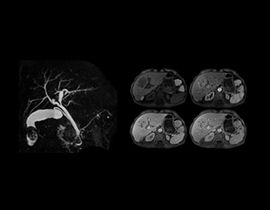

BodyWorks für einen der am schnellsten wachsenden Bereiche der MRT. Diese umfassende Bibliothek ermöglicht die Bildgebung von Abdomen und Becken und gestattet dem Benutzer die flexible Anpassung an unterschiedliche Patiententypen.

Auto Navigator ist die Lösung von GE zur Bekämpfung von Atembewegungen bei abdominellen Aufnahmen. Dieser Ansatz für freie Atmung ist mit mehreren Pulssequenzen kompatibel, darunter Diffusion, PROPELLER MB, MRCP und dynamische T1-Bildgebung.